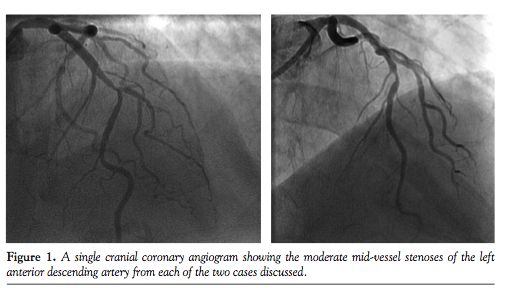

We report two cases where despite a good aortic pressure trace at the start of the procedure, there is damping of the dynamic pressure trace during hyperemia, secondary to axial migration of the guide into the left main stem (LMS). This is especially an issue with Q/CLS/EBU/Voda-shaped guiding catheters, which have more of a tendency to deeply intubate

the LMS than Judkins-shaped guides. Both of the cases involved intermediate-severity left anterior descending (LAD) arterial stenoses in middle-aged, average-sized males presenting with stable angina (Figure 1). A 6 Fr CLS 3.5 guiding catheter and a standard 0.014˝ intracoronary pressure wire (Volcano PrimeWire) via the right radial approach were used. A total of 500 µg of intracoronary nitrates were administered beforehand and hyperemia was achieved with 48 µg intracoronary injections of adenosine, as is standard for our institution.